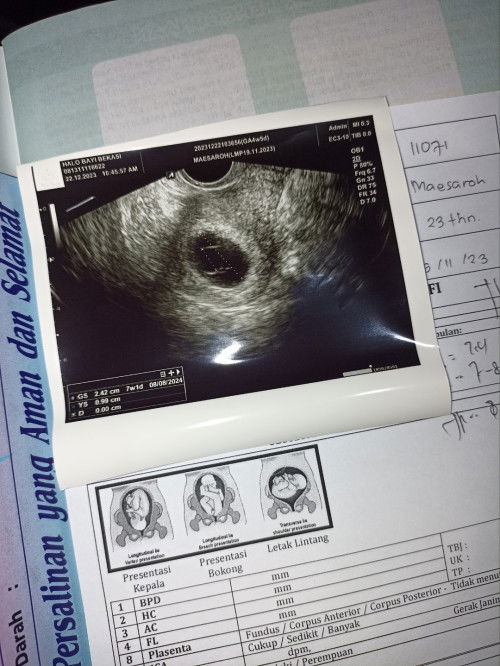

Bunda ada yang pernah hamil BO gak? Aku 30 desember keguguran krna hamil BO usia kehamilan nya 11mg, gak dikuret bun krna udah keluar sendiri tapi masih diresepin obat pembersih sama dokter, udah beberapa kali jg USG hasilnya sudah bersih. Tgl 31 januari aku haid pertama setelah keguguran, dokter nyaranin bulan maret aja kalo mau promil lagi tapi bulan februari saya udah gak haid bun alias udah positif tespeknya, kira kira aman gak ya bun kehamilan nya? Aku masih agak trauma takut terulang lagi krna jarak kehamilan nya deket sama sebelumnya, tapi aku selalu mikir positif bun kalo anak aku pasti ada dan sehat. Sharing dong bun bunda ada yang pernah ngalamin juga gak? #SeriusTanya #newmom #Sharing_dong_Bund